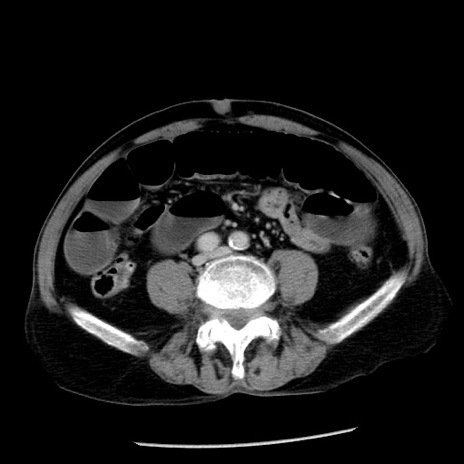

症例26(横断像)

【症例】80歳代男性

【主訴】嘔吐

【現病歴】昨晩2回嘔吐あり、今朝になっても嘔吐あり。来院。

【既往歴】胃潰瘍

【身体所見】意識清明、BT 37.6℃、BP 166/95mmHg、HR 100bpm、SpO2 97%、腹部:平坦・軟、腸蠕動音聴取良好、圧痛なし。

【データ】WBC 21900、CRP 1.46